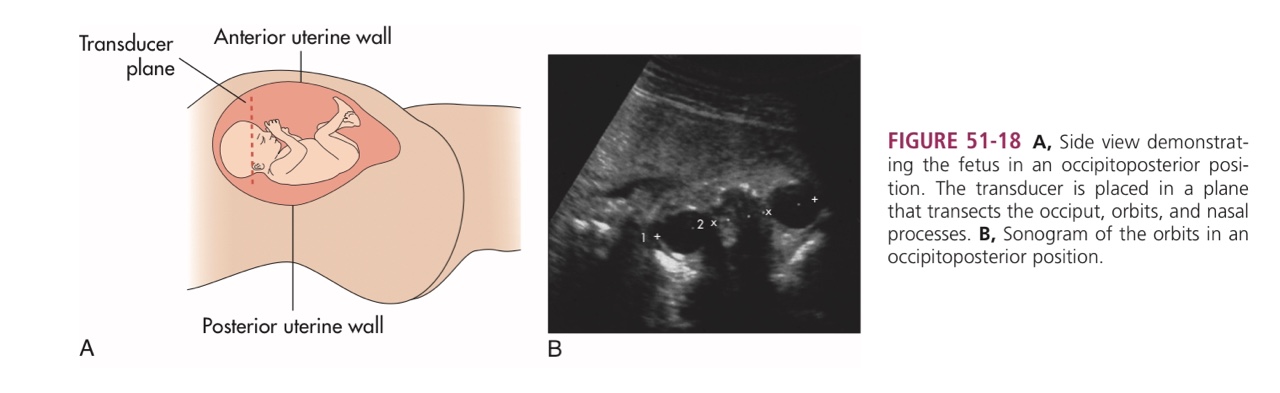

The differential diagnosis for a medial canthal mass

includes dacryocystocele,

capillary hemangioma,

solid dermoid,

dermoid cyst,

encephalocele,

meningoencephalocele,

nasal glioma,

lymphangioma,

and heterotopic brain.

Further examination did not reveal

any other pathological findings and

demonstrated normal fetal facial anatomy